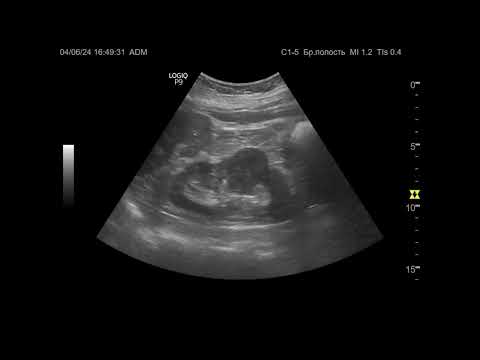

Мультипараметрическое ультразвуковое исследование желудка при опухолевом почек

Вебинар SonoScape и РАСУДМ. Лектор: Митина Лариса Анатольевна, доктор медицинских наук, ведущий научный сотрудник отделения ультразвуковой диагностики Московского научно-исследовательского онкологического института имени П.А. Герцена – филиала ФГБУ «Национальный медицинский исследовательский радиологический центр» Министерства здравоохранения Российской Федерации (г. Москва) 15.11.2017. Мастер-класс в рамках вебинара проведен на аппарате SonoScape S8Exp: